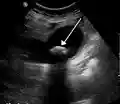

A 1.9 cm gallstone impacted in the neck of the gallbladder and leading to cholecystitis as seen on ultrasound. There is 4 mm gall bladder wall thickening.